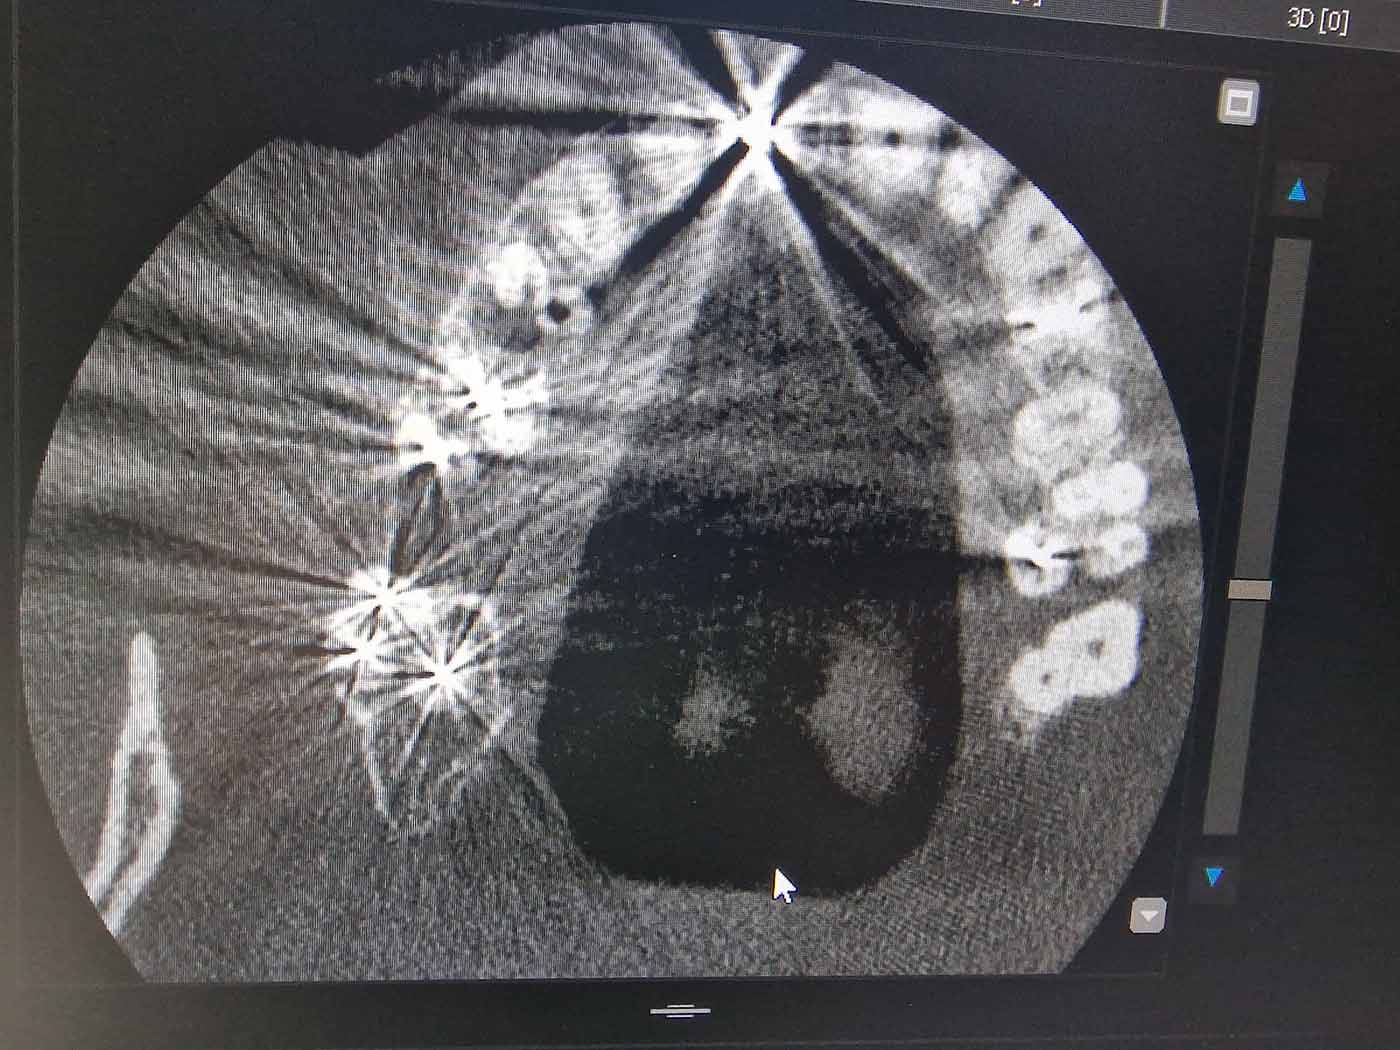

Ακολουθώντας τις πιο σύγχρονες τεχνολογικές εξελίξεις, έχουμε ενσωματώσει προηγμένα εργαλεία και μεθόδους στην ενδοδοντική θεραπεία. Χρησιμοποιούμε περιστροφικά εργαλεία τελευταίας γενιάς, σύγχρονα συστήματα έμφραξης με θερμοπλαστικοποιημένη γουταπέρκα, καθώς και ακριβείς συσκευές ανεύρεσης του μήκους των ριζικών σωλήνων, όπως το apex locator. Επιπλέον, η κλινική μας διαθέτει ψηφιακή ακτινογραφία και CBCT (αξονική τομογραφία) για την ακριβή διάγνωση και τον βέλτιστο σχεδιασμό της θεραπείας.